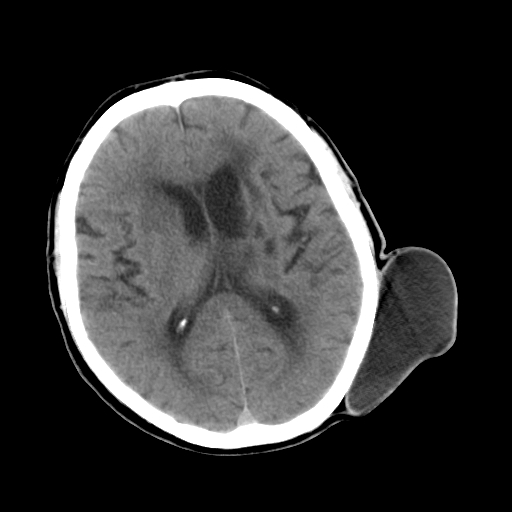

男,62岁,右侧肢体活动障碍不灵活三天,左侧头皮肿物十余年(ct值8hu)。

多发腔梗!皮下脂肪瘤!

1)多发性腔隙性脑梗塞。2)脑白质病。3)脑萎缩。4)左侧枕顶部头皮下皮样囊肿,不排除脂肪瘤。

1)多发性腔隙性脑梗塞。2)脑白质病。3)脑萎缩。4)左侧枕顶部头皮下皮样囊肿或表皮样囊肿。